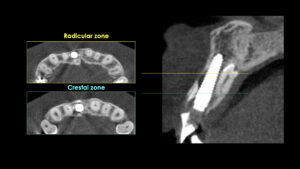

レントゲンやCTをとって精査しました。歯の根っこが破折しており、根の先端と周囲の組織が感染して炎症を起こしています。保存不可能と診断しました。正中過剰歯(余分に存在する歯)が骨の中に埋まっており、難症例ではあるがインプラント治療が最善と診断し、計画を立てていきます。

過剰歯があるので非常に薄いスペースに慎重に器具を入れていきます。「Osseodensification」という、骨を圧縮拡大していく特殊な技術を用いています。

形成した穴にインプラントを埋入しました。